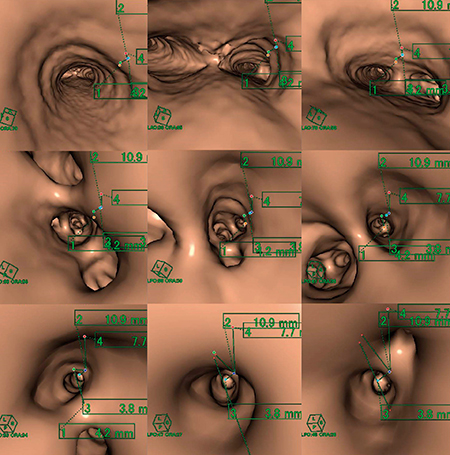

(3) 三次元画像上に点と距離が反映されるので,この点を頼りに口側から病変部までの経路を動画保存する(図5)。これで病変部への経路と位置をナビゲーションできる。

図5 画像処理:仮想気管支内視鏡画像によるナビゲーション画像

術中に気管支鏡を病変部に速やかに到達させ,位置を特定することが可能であった(図2)。執刀した担当医からも,AZE VirtualPlaceによる仮想気管支内視鏡画像が,実際の内視鏡による視野を正確に再現していたことと,病変部や気管支分岐部に目印として付けた点とその距離が三次元画像上でうまく表現され,情報として伝わりやすかったとの報告を受けている。

当施設では,TBLBの際の支援画像として,病変部の位置特定のために仮想気管支内視鏡画像を作成してきた。今回は,術中に気管支鏡を使用して位置を特定するという依頼内容であったため,応用が可能であった。評価されるべき点としては,AZE VirtualPlaceの仮想内視鏡画像作成用のアプリケーションが,ただ内側から見るだけではなく,二次元画像上の位置や距離などの情報を三次元画像上で表現でき,これによって目標や経路を特定できることと考える。また,気管支以外の臓器であってもこの機能を利用して,さまざまな手技に対しての手術支援画像を作成することが可能であると考える。